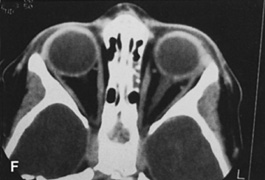

Fig. 25. A,B. Coronal (A) and axial (B) CT scans demonstrating well-encapsulated mass posteriorly in the superonasal orbit. An excellent alternative to transcranial orbitotomy for this lesion is an anterior approach via a vertical-lid splitting incision.

The upper eyelid crease incision gives excellent access to the peripheral superior orbital space. However, lesions that lie intraconally are difficult to approach with a transverse lid crease incision as dissection must be performed medial to the medial horn of the levator muscle to avoid transecting and disinserting the levator aponeurosis and Müller's muscle. However, vertically splitting the upper lid allows a vertical separation of the levator aponeurosis and Müller's muscle and does not disinsert it from its normal insertions on the tarsal plate. This approach provides an excellent exposure of the superomedial orbit and is useful for approaching lesions that lie medial to the optic nerve.26 In this situation, it is often an attractive alternative to a transcranial superior orbitotomy, which might otherwise be required (Fig. 25).

VERTICAL-LID-SPLIT SUPERIOR ORBITOTOMY